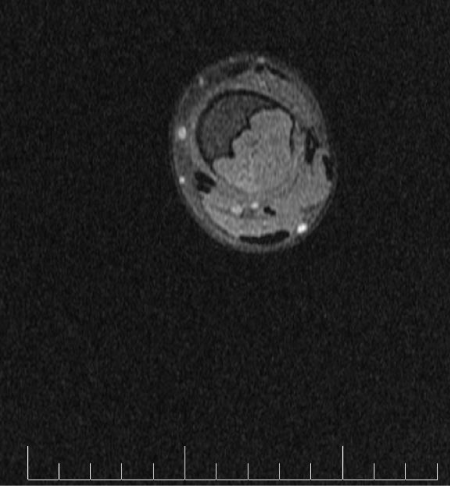

MRI demonstrates low signal intensity on T1 weighted images (Figure 2, Figure 11 and Figure 12). T2 weighted images demonstrate high signal intensity (Figure 3, Figure 13). Post gadolinium contrast T1 weighted sagittal view demonstrates diffuse heterogenous enhancement (Figure 14). Post gadolinium contrast T1 weighted axial view demonstrates peripheral nodular enhancement (Figure 15).

Figure 15: MRI axial T1 fat sat post gadolinium of the left tibia.

Treatment consists of curettage or en-bloc resection [6]. Curettage alone has a higher recurrence rate compared to curettage combined with bone grafting [6]. Recurrence rates as noted by Gherlinzoni F et al, were noted to be as high as 80% with curettage alone and dropping to 7% when combined with bone grafting [7]. Long bone lesions are preferably treated with either en bloc or curettage combined with bone grafting as in our case [8].